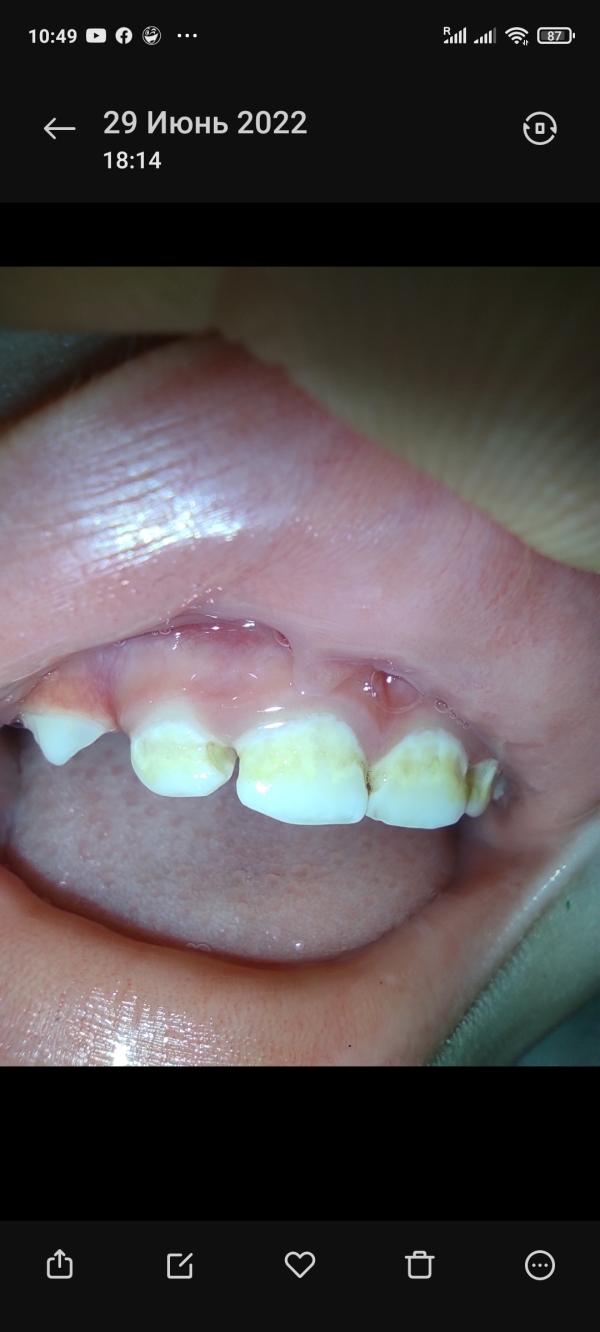

Фото прикрепряю(смотрите дату с какой скоростью портятся зубки)

Они становились жёлтые, фото буду прикреплять. Тут стоматологи говорят очень разные предположения. То флюороз, то кариез, я не знаю что думать и чем лечить. Флюороз - переизбыток фтора(в польше мы купили детскую зубную пасту, в составе был фтор, он предотвращает кариез), Кариез - сказали что начальная стадия, зубки портятся из-за того что грудное молоко остаётся под губой, лечить сказали так:"чаще чистить зубки пастой с ФТОРОМ"

У меня патовая ситуация, 2 варианта, один из них - убьёт зубы. Но это малость моих проблем уже. Вчера вечером мы пошли в детскую комнату, дети играли, и Милош ударился зубами об горку, в итоге минус половина переднего зуба. Стоматолога(детского!) в нашем городе нет, только в поликлинике(он сказал кариез)

Карієс там теж може бути, але як на мене (не стоматолог!), то нетипова картина. Але ми всі індивідуальні.